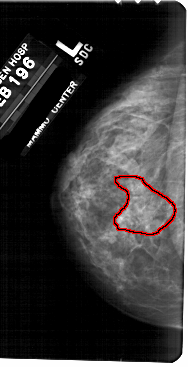

A_1724_1.LEFT_CC

LEFT_CC LINES 5491 PIXELS_PER_LINE 2806 BITS_PER_PIXEL 12 RESOLUTION 43.5 OVERLAY

FILE: A_1724_1.LEFT_CC.OVERLAY

TOTAL_ABNORMALITIES 1

ABNORMALITY 1

LESION_TYPE CALCIFICATION TYPE PLEOMORPHIC-FINE_LINEAR_BRANCHING DISTRIBUTION SEGMENTAL

ASSESSMENT 4

SUBTLETY 3

PATHOLOGY MALIGNANT

TOTAL_OUTLINES 1

BOUNDARY